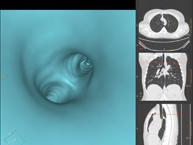

- Broncoscopia virtual La broncoscopia virtual es una técnica no invasiva que permite la visualización tridimensional y bidimensional de la tráquea y del árbol bronquial mediante la toma secuencial de imágenes captadas con TC Multidetector, obteniendo imágenes bi y tridimensionales. La calidad de las imágenes permite la navegación virtual por el interior de la tráquea y de los bronquios gracias al procesamiento en estaciones de trabajo especializadas. La broncoscopia virtual es una técnica no invasiva que permite la visualización tridimensional y bidimensional de la tráquea y del árbol bronquial mediante la toma secuencial de imágenes captadas con TC Multidetector, obteniendo imágenes bi y tridimensionales. La calidad de las imágenes permite la navegación virtual por el interior de la tráquea y de los bronquios gracias al procesamiento en estaciones de trabajo especializadas.

- Colonoscopia virtual  La colonoscopia virtual es una técnica no invasiva que permite la visualización tridimensional y bidimensional del intestino grueso o del colon mediante la toma secuencial de imágenes captadas con TC Multidetector de última generación. La calidad de las imágenes permite la navegación virtual por el interior del recto y del colon gracias al procesamiento en estaciones de trabajo especializadas. La preparación de la prueba consiste en realizar una dieta baja en fibra tres días antes de la prueba (para limpiar el colon y el recto) y de la ingestión de contraste oral yodado el día antes de la prueba (para marcar las heces y poder distinguirlas correctamente de las posibles lesiones colónicas). A diferencia de la fibrocolonoscopia, no se requiere sedación ni soluciones evacuantes. La prueba se realiza en la sala del TC donde, a través de un pequeño tubo flexible, se insufla aire para distender el colon. La colonoscopia virtual es una técnica no invasiva que permite la visualización tridimensional y bidimensional del intestino grueso o del colon mediante la toma secuencial de imágenes captadas con TC Multidetector de última generación. La calidad de las imágenes permite la navegación virtual por el interior del recto y del colon gracias al procesamiento en estaciones de trabajo especializadas. La preparación de la prueba consiste en realizar una dieta baja en fibra tres días antes de la prueba (para limpiar el colon y el recto) y de la ingestión de contraste oral yodado el día antes de la prueba (para marcar las heces y poder distinguirlas correctamente de las posibles lesiones colónicas). A diferencia de la fibrocolonoscopia, no se requiere sedación ni soluciones evacuantes. La prueba se realiza en la sala del TC donde, a través de un pequeño tubo flexible, se insufla aire para distender el colon.